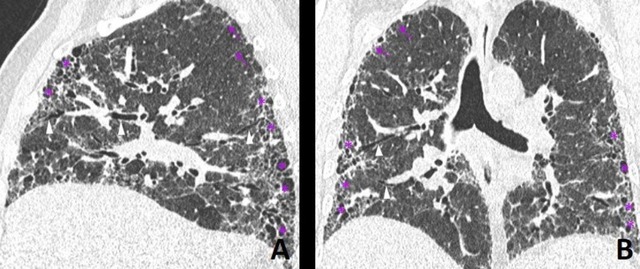

Hình ảnh CT ngực cho thấy phổi người bệnh IPF với mô xơ hóa dạng “tổ ong”.

Sử dụng chụp CT ngực độ phân giải cao để thấy các dấu hiệu như "honeycombing" (tổ ong), traction bronchiectasis, mô xơ.